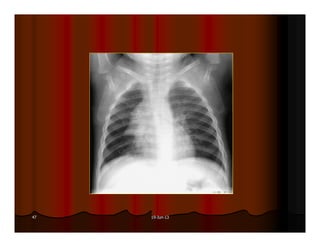

Phim phaûi ñöôïc chuïp ôû tö theá thaät ngay

thaúng: Khoaûng caùch töø ñaàu trong xöông

ñoøn hai beân ñeán maáu gai ñoát soáng baèng

nhau (ñoái vôùi treû em thì so saùnh khoaûng

caùch töø ñaàu trong cung söôøn tröôùc ñeán

ñöôøng giöõa).

Được xem là cân đối khi khoảng cách từ đầu trong của xương

đòn hai bên đến gai sống bằng nhau.